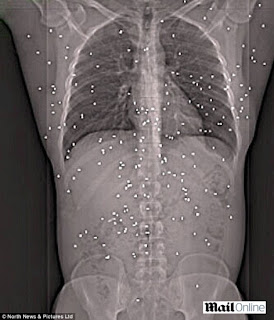

O radiografie arata ranile ingrozitoare pe care un barbat de 33 de ani le-a capatat in urma unui atac armat din 2007. Agresorii l-au impuscat in spate de 150 de ori. Joe Clarke a supravietuit, insa medicii nu i-au putut scoate niciuna dintre alice.

In decembrie 2007, doi barbati au tras asupra lui Joe Clarke, in momentul in care acesta a deschis usa casei sale din Fairways, Consett, Durham. Alicele de otel sau plumb i-au strapuns spatele, capul si gatul. A supravietuit atacului, pentru ca un vecin l-a gasit la timp si i-a acordat primul ajutor.

Joe inca mai simte efectele atacului in urma caruia are dureri permanente. Medicii spun ca nu au mai vazut niciodata asa ceva si i-au explicat ca nu pot sa-i scoata alicele, pentru ca acestea au patruns prea adanc in corp si i-au atins organe vitale.